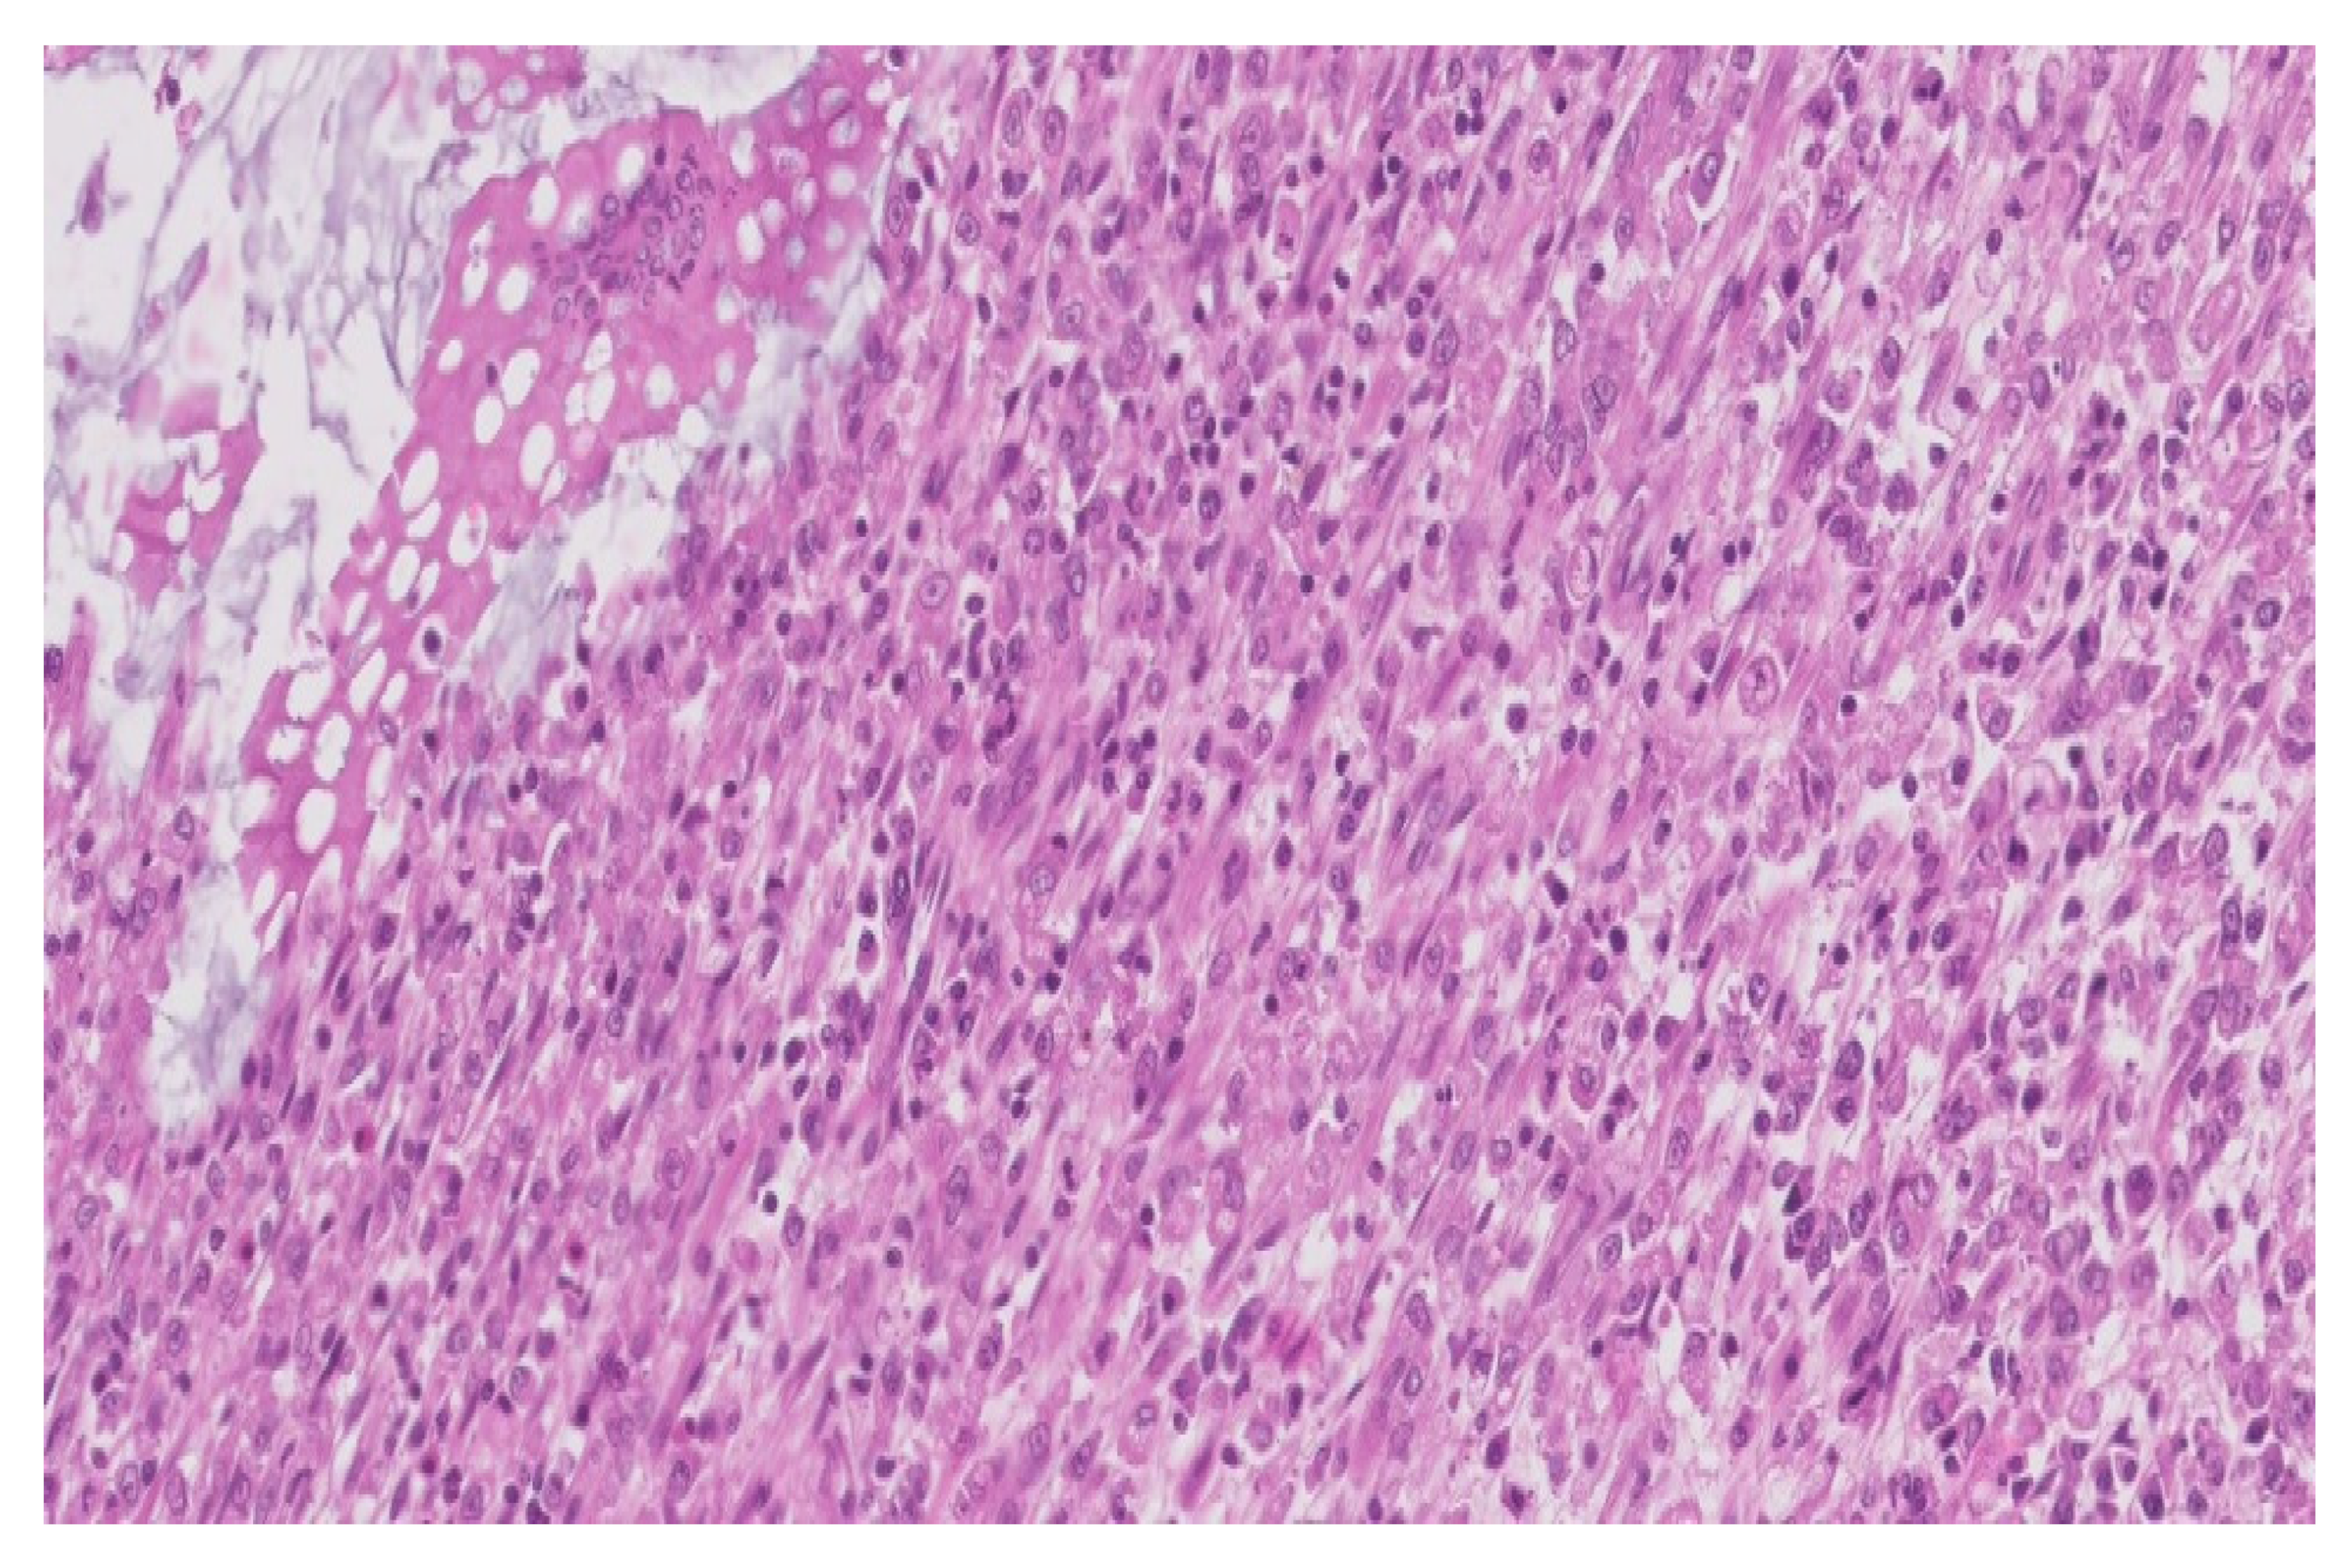

Figure 3.

Dense macrophage infiltrate with rare dispersed lymphocytes (HE, ×200).

The microscopic examination revealed:

- a significant architectural remodeling of the colonic mucosa and submucosa with dense cellular inflammatory infiltrate,

- the dense cellular inflammatory infiltrate-composed of epithelioid macrophages with wide eosinophilic cytoplasm, variable-sized nuclei, with occasional nucleoli,

- dispersed syncytia with the appearance of multinucleated giant cells, with chaotically disposed nuclei and

- amorphous cytoplasmatic inclusions of cellular detritus type, with sporadic intercalated lymphocytes.

Neither areas of necrosis, nor viable microorganisms were detected.